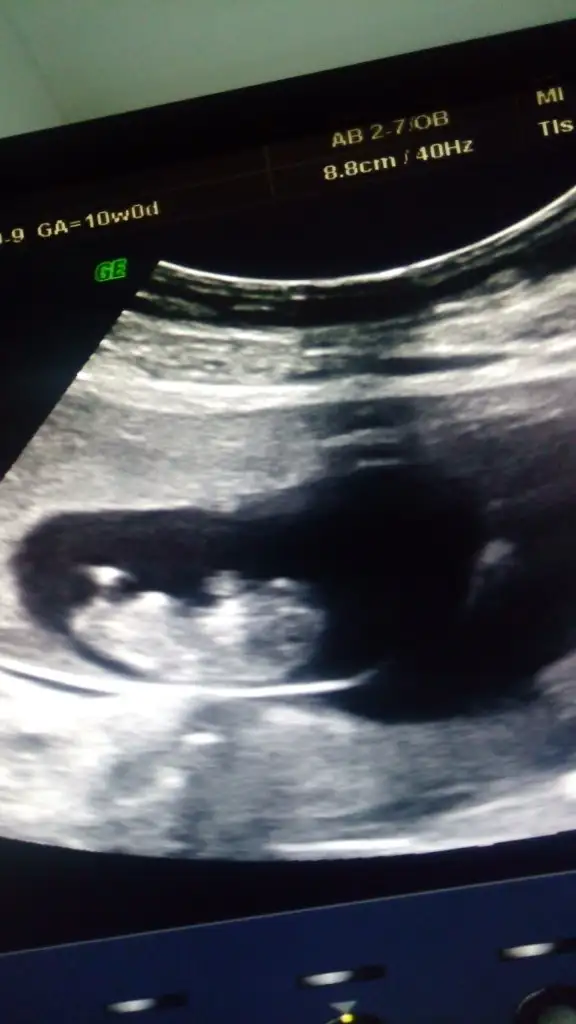

Vajinalsa kız karındansa erkekKizlar Merhaba

Benim ultrason goruntumude yorumlayabilecek olan var mı? 6.2 haftalik karından goruntumuz.

Eki Görüntüle 2301203